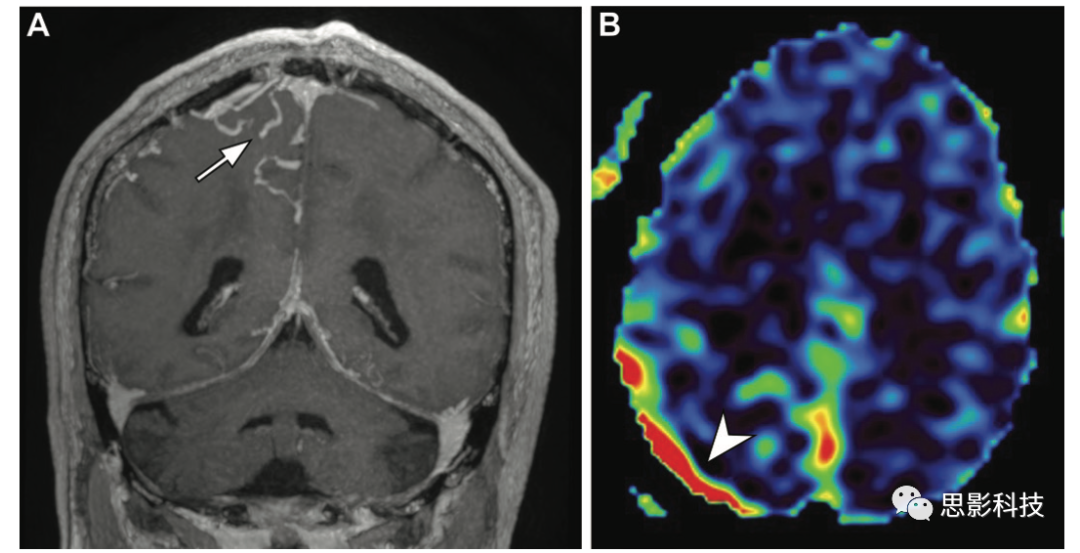

腦部典型軟腦膜型動(dòng)靜脈畸形,患者為34歲女性,癲癇發(fā)作。(A,B)軸位T2加權(quán)像和冠狀位高空間分辨率增強(qiáng)T1加權(quán)像顯示多個(gè)血流空隙,血管病灶的特征是右側(cè)頂葉內(nèi)嵌有一團(tuán)強(qiáng)化的管狀結(jié)構(gòu)(箭頭)。(C)ASL MRI表現(xiàn)為靜脈ASL信號(hào)偽影,表現(xiàn)為由于動(dòng)靜脈分流或快速傳輸,病灶(箭頭)和引流靜脈(箭頭)信號(hào)增強(qiáng)。